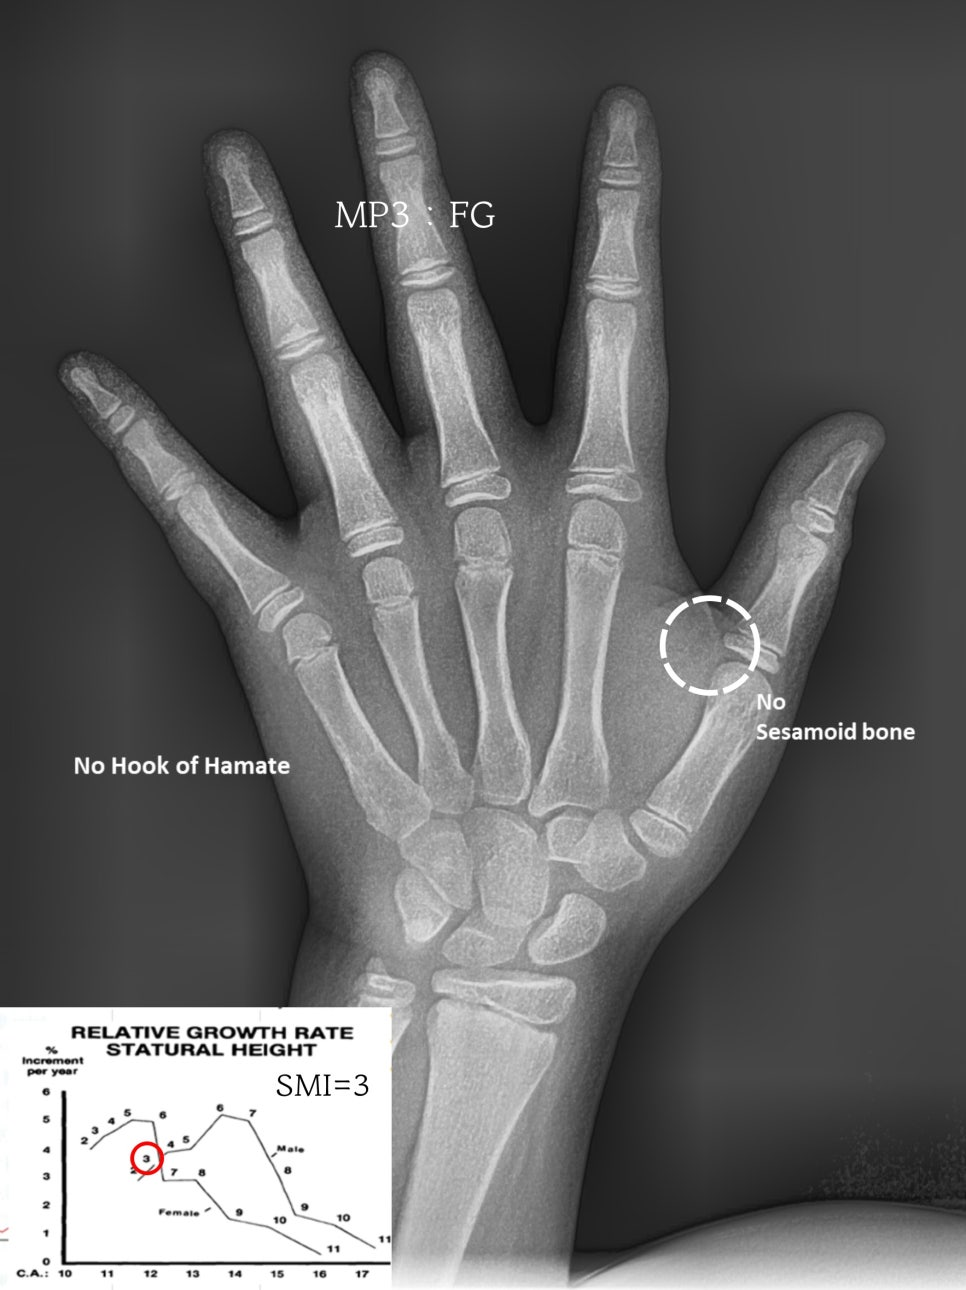

수완부 촬영 검사를 통해

성장이 끝났는지, 남았는지 그리고

어느 단계쯤에 와있는지를 파악할 수 있습니다.

종자골(sesamoid bone)은

엄지손가락의 하단부에 위치해 있으며

아직 자라지 않은 것으로 보아

성장기 피크 직전으로 판단되었습니다.